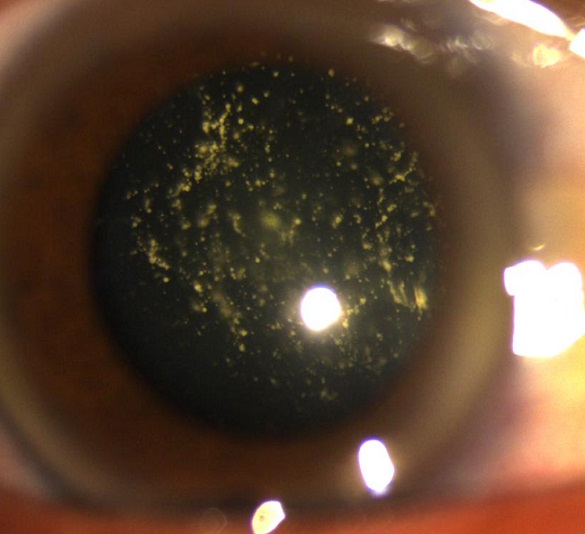

Low visual acuity and asteroid hyalosis

A 56 years old man was admitted to the ophthalmology department for low visual acuity since his 45 years old with no amelioration after optic correction. The physical exam found visual acuity at 1/10 on the right eye and 9/10 on the left one, clear cornea, intraocular pressure at 14 mmhg on both eyes, the fundus of the right eye showed multiple yellow mobile vitreous particles that are absent on the left fundus. Asteroid hyalosis is a degenerative condition of the eye involving small white opacities in the vitreous humor. Clinically, these opacities are quite refractile, giving the appearance of stars (or asteroids) shining in the night sky except that ocular asteroids are often quite mobile. Ocular asteroids must be distinguished from the more common typical vitreous floaters, which are usually fibrillar or cellular condensates. The cause of asteroid hyalosis is unknown, but it has been associated with diabetes mellitus, hypertension and hypercholesterolemia. The asteroid bodies are made up of hydroxylapatite, which in turn consists of calcium and phosphates or phospholipids. While asteroid hyalosis does not usually severely affect vision, the floating opacities can be quite annoying, and may interfere significantly with visualization and testing of the retina. The treatment of asteroid hyalosis is usually unnecessary, vitrectomy may occasionally be indicated, for both diagnostic and therapeutic purposes.